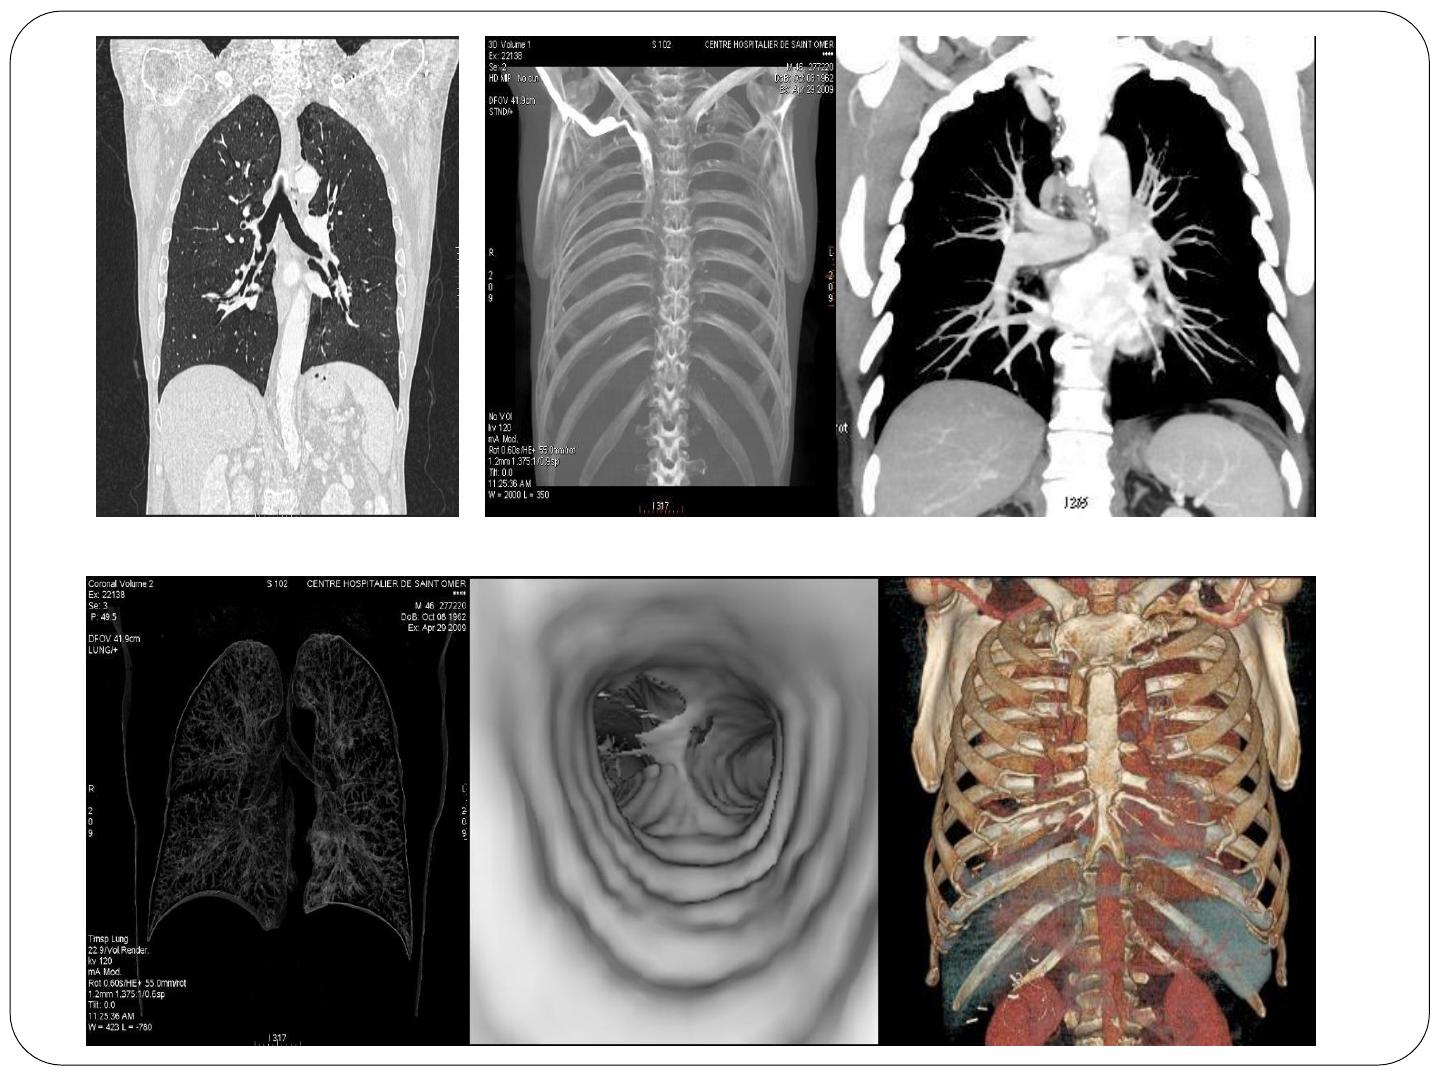

TDM de la région thoracique : Protocoles et techniques

TDM DE LA RÉGION

THORACIQUE

L’exploration TDM du thorax permet une étude détaillée :

du contenu de la cavité thoracique : plèvre, poumons

(parenchyme), médiastin, gros vaisseaux, œsophage,

de la cage thoracique (cotes, vertèbres dorsales, sternum, omoplate).